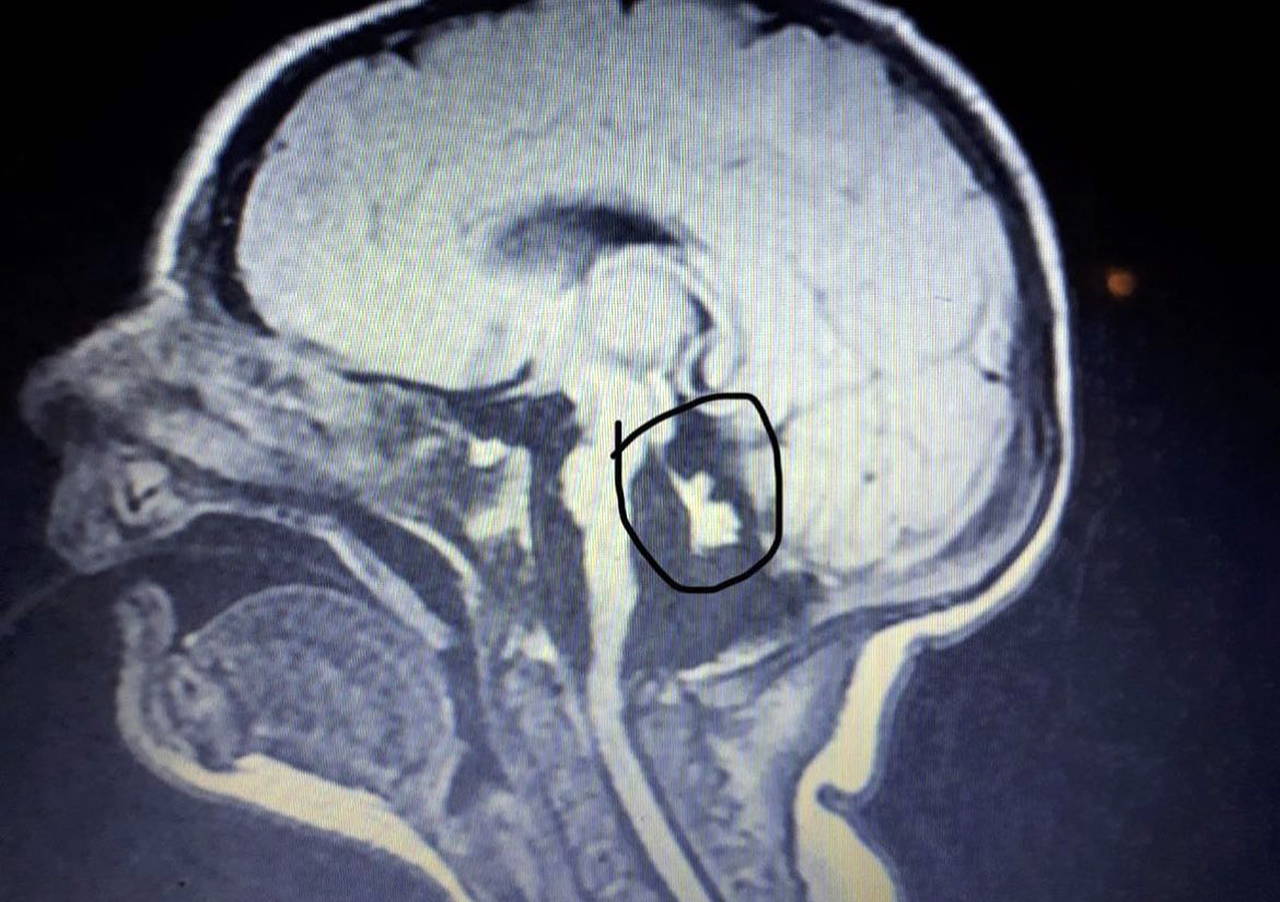

GERÇEK, ÜNİVERSİTE HASTANESİNDE ORTAYA ÇIKTI

MRG sonuçlarını göstermek için Akdeniz Üniversitesi Hastanesi'ne gittiğini kaydeden Tarık Özdemir, "Akdeniz Üniversitesi değerlendirdiğinde, gerçek ortaya çıktı. Ata'nın beyinciği neredeyse hiç yoktu. Doktorlar, 'Beyin sapı tamamen bozuk. 2-3 ay belki yaşar' dedi. Ata'da ağır epilepsi ve mikrosefali vardı. MRG görüntüsünde beyinciği olmadığı görülüyor ama özel hastane radyoloğu bunu göremiyor. Aslında anne karnında tespit edilmesi gereken hastalıklar. Özellikle detaylı ultrason taramaları bunun için yapılıyor ama hiçbir şekilde anlamıyorlar, doğduktan sonra da farkına varmıyorlar, 'sağlıklı' diye rapor tuttular" diye konuştu.